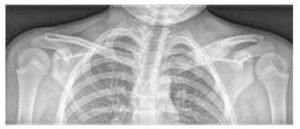

З кісток найчастіше уражаються метафізи довгих кісток, ключиця, тіла хребців і таз (див. малюнок № 2). Кількість кісткових уражень є змінною (іноді лише поодиноке вогнище, частіше множинні). Іноді навіть безсимптомні ураження виявляють кісткова сцинтиграфія або магнітно-резонансна томографія всього тіла (WB MRI).

Основним обстеженням є нативне РТГ симптоматичних ділянок (див. малюнок № 3), доповнене обстеженням за допомогою магнітно-резонансної томографії та/або комп’ютерної томографії.

Зображення № 1

Пальмоплантарна пустульоз у пацієнтки з CRMO

Зображення № 2

Порівняння розподілу кісткових вогнищ на МРТ дітей з CRMO та септичним остеомієлітом (за Schnabel et al., 2016)

Зображення № 3

Розширення та остеолітичні ураження медіального кінця лівої ключиці та набряк м’яких тканин на РТГ